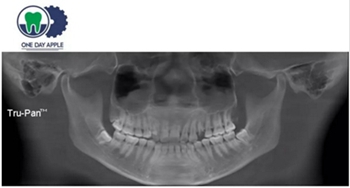

患者、男、40歲,下頜牙缺失數(shù)年來院咨詢種植。

檢查:46缺失, 47傾斜, 1度松動, 未見48萌出,

CBCT:骨量高度及寬度可, 48埋伏,低位阻生.37近中骨吸收

診斷:下頜牙列缺損, 48低位埋伏阻生 37 牙周炎

治療計劃:46種植, 同期拔除48 正畸扶正47.